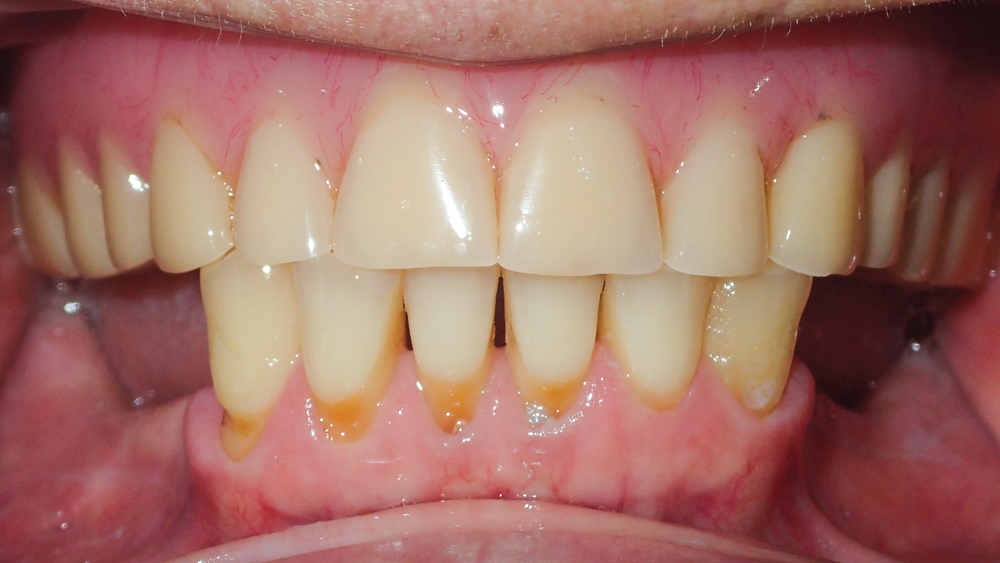

CASE REPORT

The following case highlights the efficient, user-friendly scanning capabilities of the iTero Element scanner, as well as the clinical advantages of connecting to the glidewell.io In-Office Solution for single-appointment dental restorations. The patient sought treatment for a damaged mandibular first molar with a cusp fracture. Because the case called for a single crown and high-strength zirconia, the patient was an ideal candidate for a same-visit restoration milled from a BruxZir NOW milling block. After preparing the tooth and taking an intraoral scan, the crown was fabricated within 40 minutes using the fastmill.io In-Office Unit. The final restoration fit perfectly without adjustment and exceeded the expectations of the patient, who was thrilled that she didn’t have to schedule a second appointment for the crown delivery.